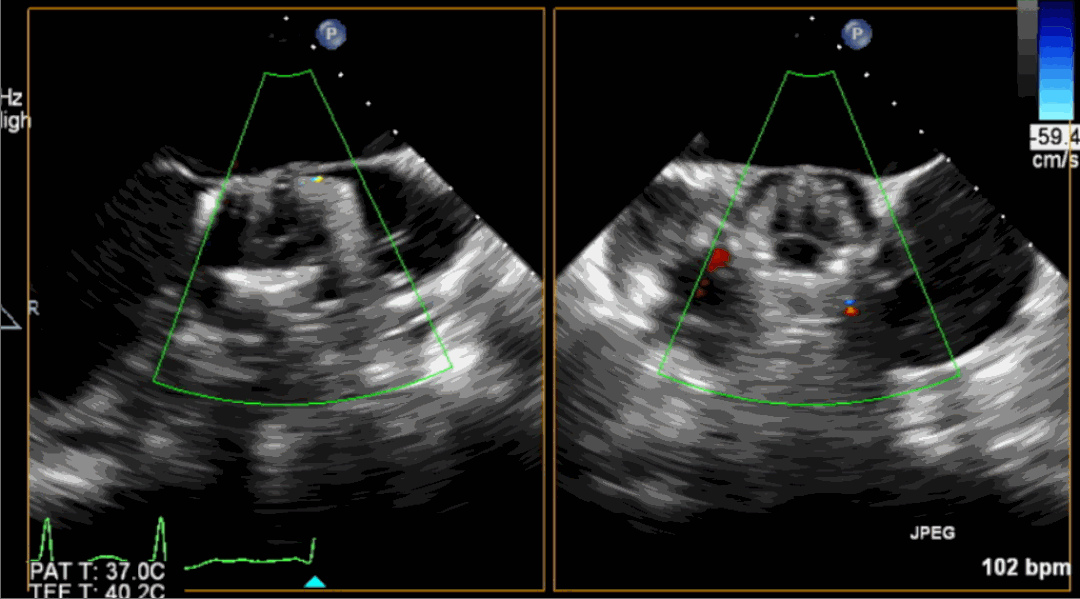

手術(shù)采用經(jīng)心尖入路,對患者進(jìn)行全麻后,在左側(cè)心尖處做3-4cm微創(chuàng)手術(shù)切口,在DSA及超聲引導(dǎo)下手術(shù)順利完成。從導(dǎo)入器械到完成瓣膜置入,僅耗時約10分鐘。術(shù)后即刻主動脈瓣返流程度由術(shù)前大量返流轉(zhuǎn)為消失,患者于導(dǎo)管室拔除氣管插管,次日由ICU轉(zhuǎn)入普通病房。

術(shù)中釋放定位鍵后DSA影像圖

術(shù)中瓣膜釋放過程

術(shù)后超聲影像圖